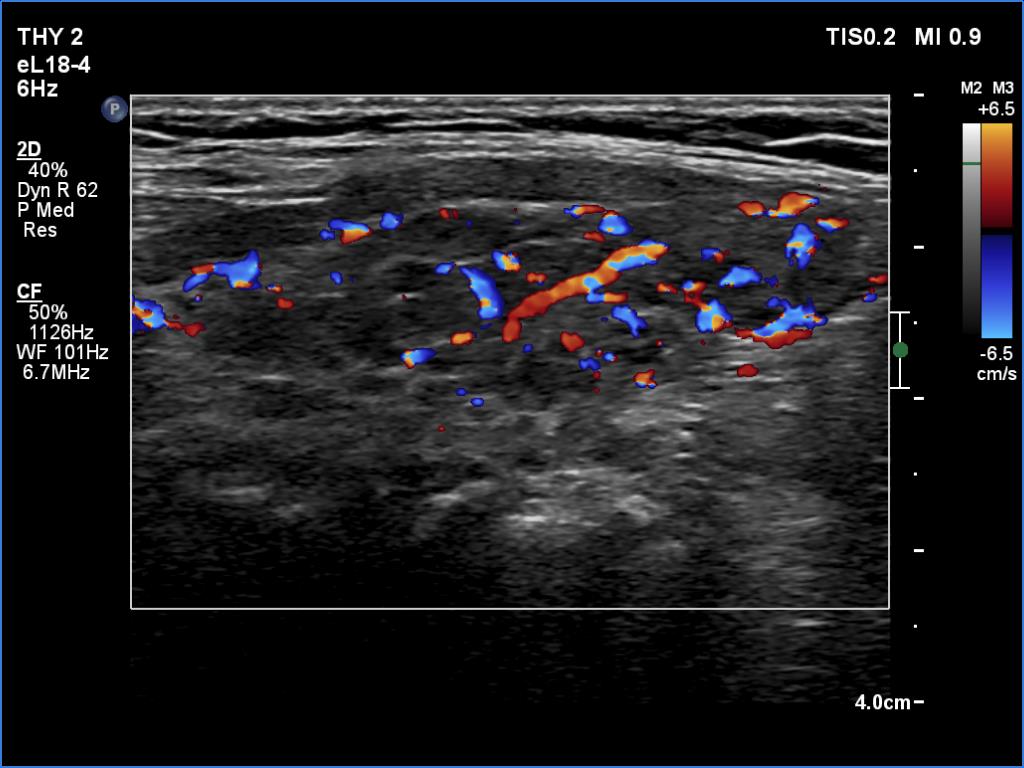

Clinical data: A 57-year-old woman was referred for evaluation of an elevated aTPO level detected on screening.

Laboratory tests: TSH 1.85 mIU/L, aTPO > 1300 U/mL.

Ultrasonography. The thyroid was minimally hypoechoic and had several discrete areas of various echogenicities. None of these lesions corresponded to true nodule.